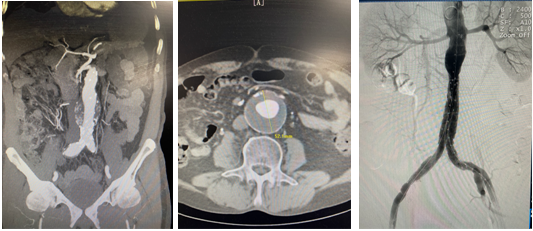

近日,六合彩网站血管外科在代毅主任带领下,李伟主治医师、侯峰主治医师、刘斐住院医师成功开展六合彩网站首例Yuranos腹主动脉覆膜支架治疗腹主动脉瘤合并右髂总动脉瘤手术,精准定位封闭瘤腔的同时保留患者盆腔血供,解除“双定时炸弹”,挽救患者生命。

本例腹主动脉瘤患者瘤颈长度3.6cm,瘤颈角度30.7°,瘤体直径5.28cm,瘤腔内血栓直径2.9cm,右侧髂总动脉瘤直径2.02cm。患者腹主动脉瘤瘤体直径较大,瘤腔内血栓较多,瘤体破裂及血栓脱落导致远端栓塞风险高,且合并右侧髂总动脉瘤,手术指征明确。术前在代毅主任指导下,医护团队积极完善相关术前检查,并组织了多次科内术前讨论,对手术方式、术中术后的风险及并发症、术后护理等均制定了详细计划及预案,确保手术安全顺利进行。本例手术难点在于合并右侧髂总动脉瘤,且累及右髂内动脉,术中、术后易发生远端型内漏、移植物移位、肾动脉闭塞等并发症。术中需栓塞右髂内动脉,所以必须精确定位左侧髂支支架的位置,保留左髂内动脉,确保盆腔血供。经充分评估患者病情及征得患者及家属同意后,详细制定手术方案,最终顺利完成手术。